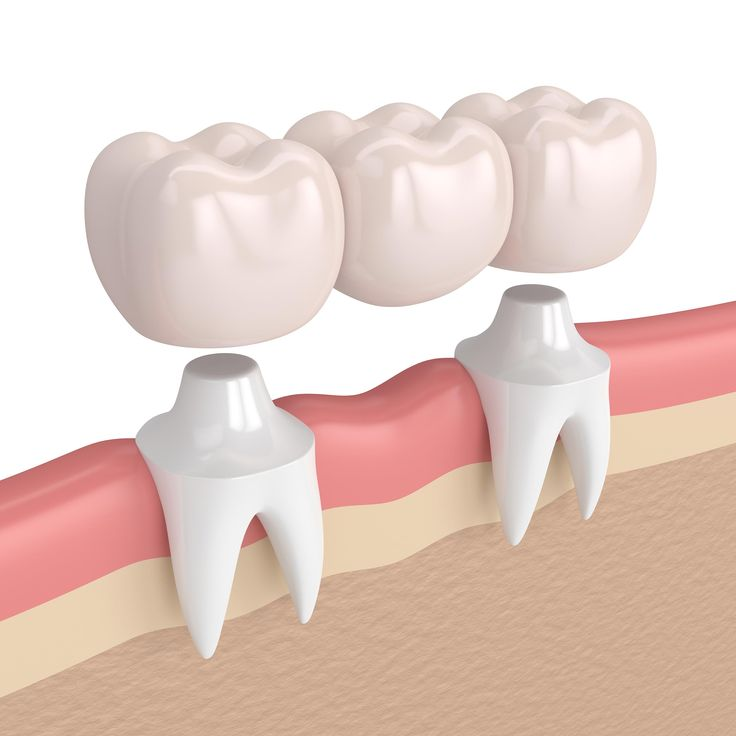

Replace missing teeth and restore your smile with our custom dental bridges. Our bridges are designed to look natural, function properly, and prevent the remaining teeth from shifting, providing a permanent solution for tooth loss.

- ✔ Traditional fixed bridges

- ✔ Porcelain and metal bridges